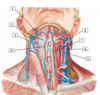

1 - facial artery and vein

2 - retromandibular vein

3 - external jugular vein

4 - anterior jugular vein

5 - common carotid artery

6 - internal jugular vein

7 - superior thyroid artery and vein

8 - external carotid artery

#1

#1 - facial artery and vein

#2

137

#3 - external jugular vein

#4

139

#5 - common carotid artery

#6

141

#7 - superior thyroid artery and vein

#8